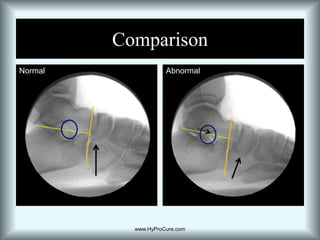

What’s NormalTalus is sitting on top of the calcaneus

Articulating facets are in complete contact

Sinus tarsi is in an “open” position

Cyma Line normal

Navicular elevatedwww.HyProCure.com

What’s AbnormalTalus not sitting on top of the calcaneus

Articulating facets are partially displaced

Sinus tarsi is partially collapsed/obliterated

Anterior deviated Cyma

Navicular has dropped.www.HyProCure.com

ComparisonNormalAbnormalwww.HyProCure.com